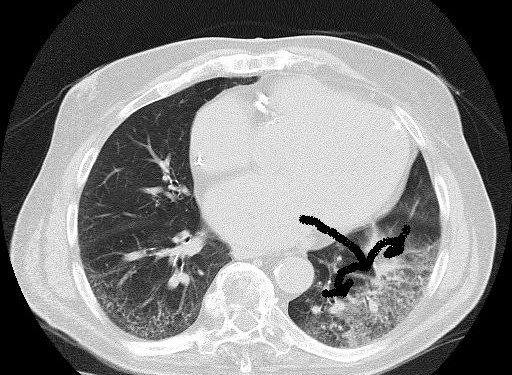

| Akciğer radyogramında multilober infiltratlar |